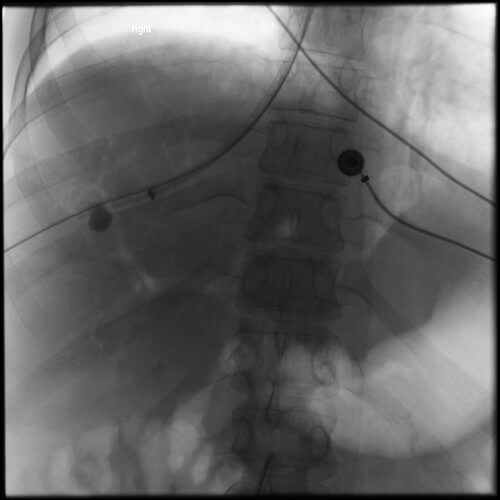

Comment: Attempts were made to place a TIPS in this patient from a hepatic vein approach. However, no recognizable hepatic veins were evident and no collaterals could be accessed percutaneously. As a result, we placed an 18g Chiba needle using a transhepatic approach from the midaxillary line; the needle was directed towards the RA-IVC junction. At the same time, the right internal jugular vein was accessed and a snare was positioned in the upper IVC. The needle was directed towards and passed through the snare. A guidewire was then advanced through the needle and that wire was pulled into the IJ sheath by the snare. A 5F sheath was then advanced from the liver into the IVC and a second wire was placed through the sheath and captured (in order to have a safety wire). At this point, the intrahepatic tract was dilated and a 10F sheath was advanced from the neck into this new tract through the liver. A CO2 venogram was then performed, followed by creation of a TIPS through this tract, extending from the right portal vein into IVC. Note that once the first stent was in place, it was short of the IVC so additional stents had to be placed. In addition, thrombus was noted at the origin of the right portal vein with preferential flow into the left portal vein. Mechanical thrombectomy had to be performed to insure portal vein and TIPS patency. At the conclusion of the procedure, the portosystemic pressure gradient decreased from 39 mm Hg to 10 mm Hg.